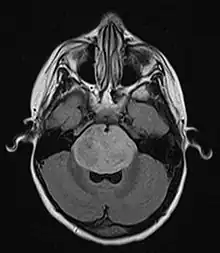

| Brain stem glioma. MRI axial, with contrast | |

Neuroimaging, such as MRI, is the main diagnostic tool for brain stem gliomas. In very rare cases, surgery and biopsy are performed.